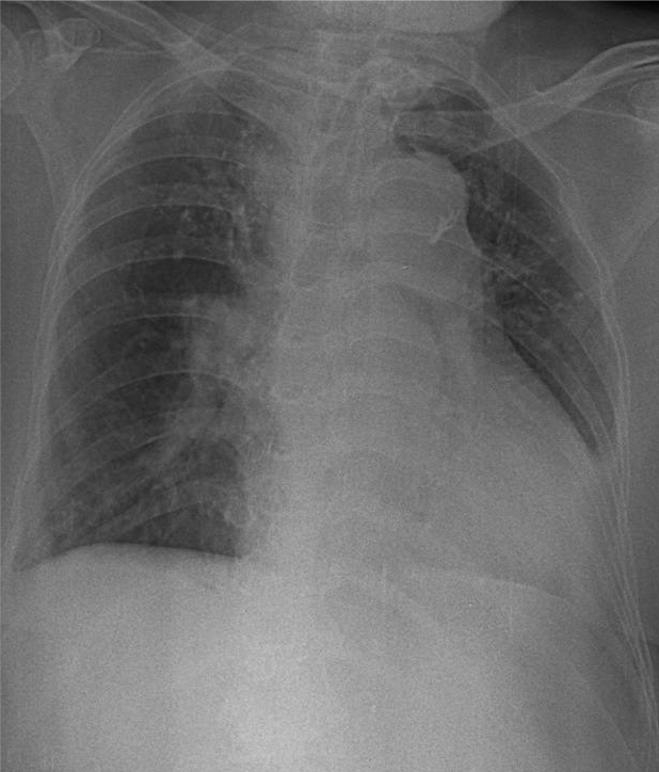

Hãy phân tích tình huống NỮ 80 tuổi -CĐ:Di chứng nhồi máu não, tiêu chảy cấp

1-Dụng cụ mở khí quản ra da(canul) 2-Tim to 3-Cung động mạch chủ đóng vôi